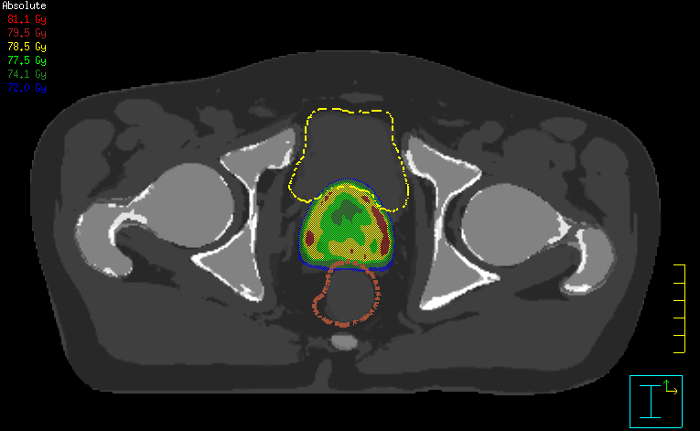

Innovative strategies in MRI-only simulation have made it possible to derive CT-like electron density information from MR imaging data. This capability enables physicians to use MRI as the radiotherapy department’s primary imaging modality for specific applications to eliminate tedious and error-prone CT-MR registration and simplify workflows.

This not only extends the benefits of MRI’s excellent soft-tissue contrast to radiotherapy planning, but it also eliminates arduous, error-prone CT-MRI registration from the process, reducing uncertainties and complexity. MR-only radiotherapy

Our innovative MRCAT (MR for Calculating ATtenuation) clinical applications lets you plan radiation therapy using MRI as primary imaging modality. Within just one, fast MR exam, MRCAT provides both excellent soft-tissue contrast for target and OAR delineation and CT-like density information for dose calculations.